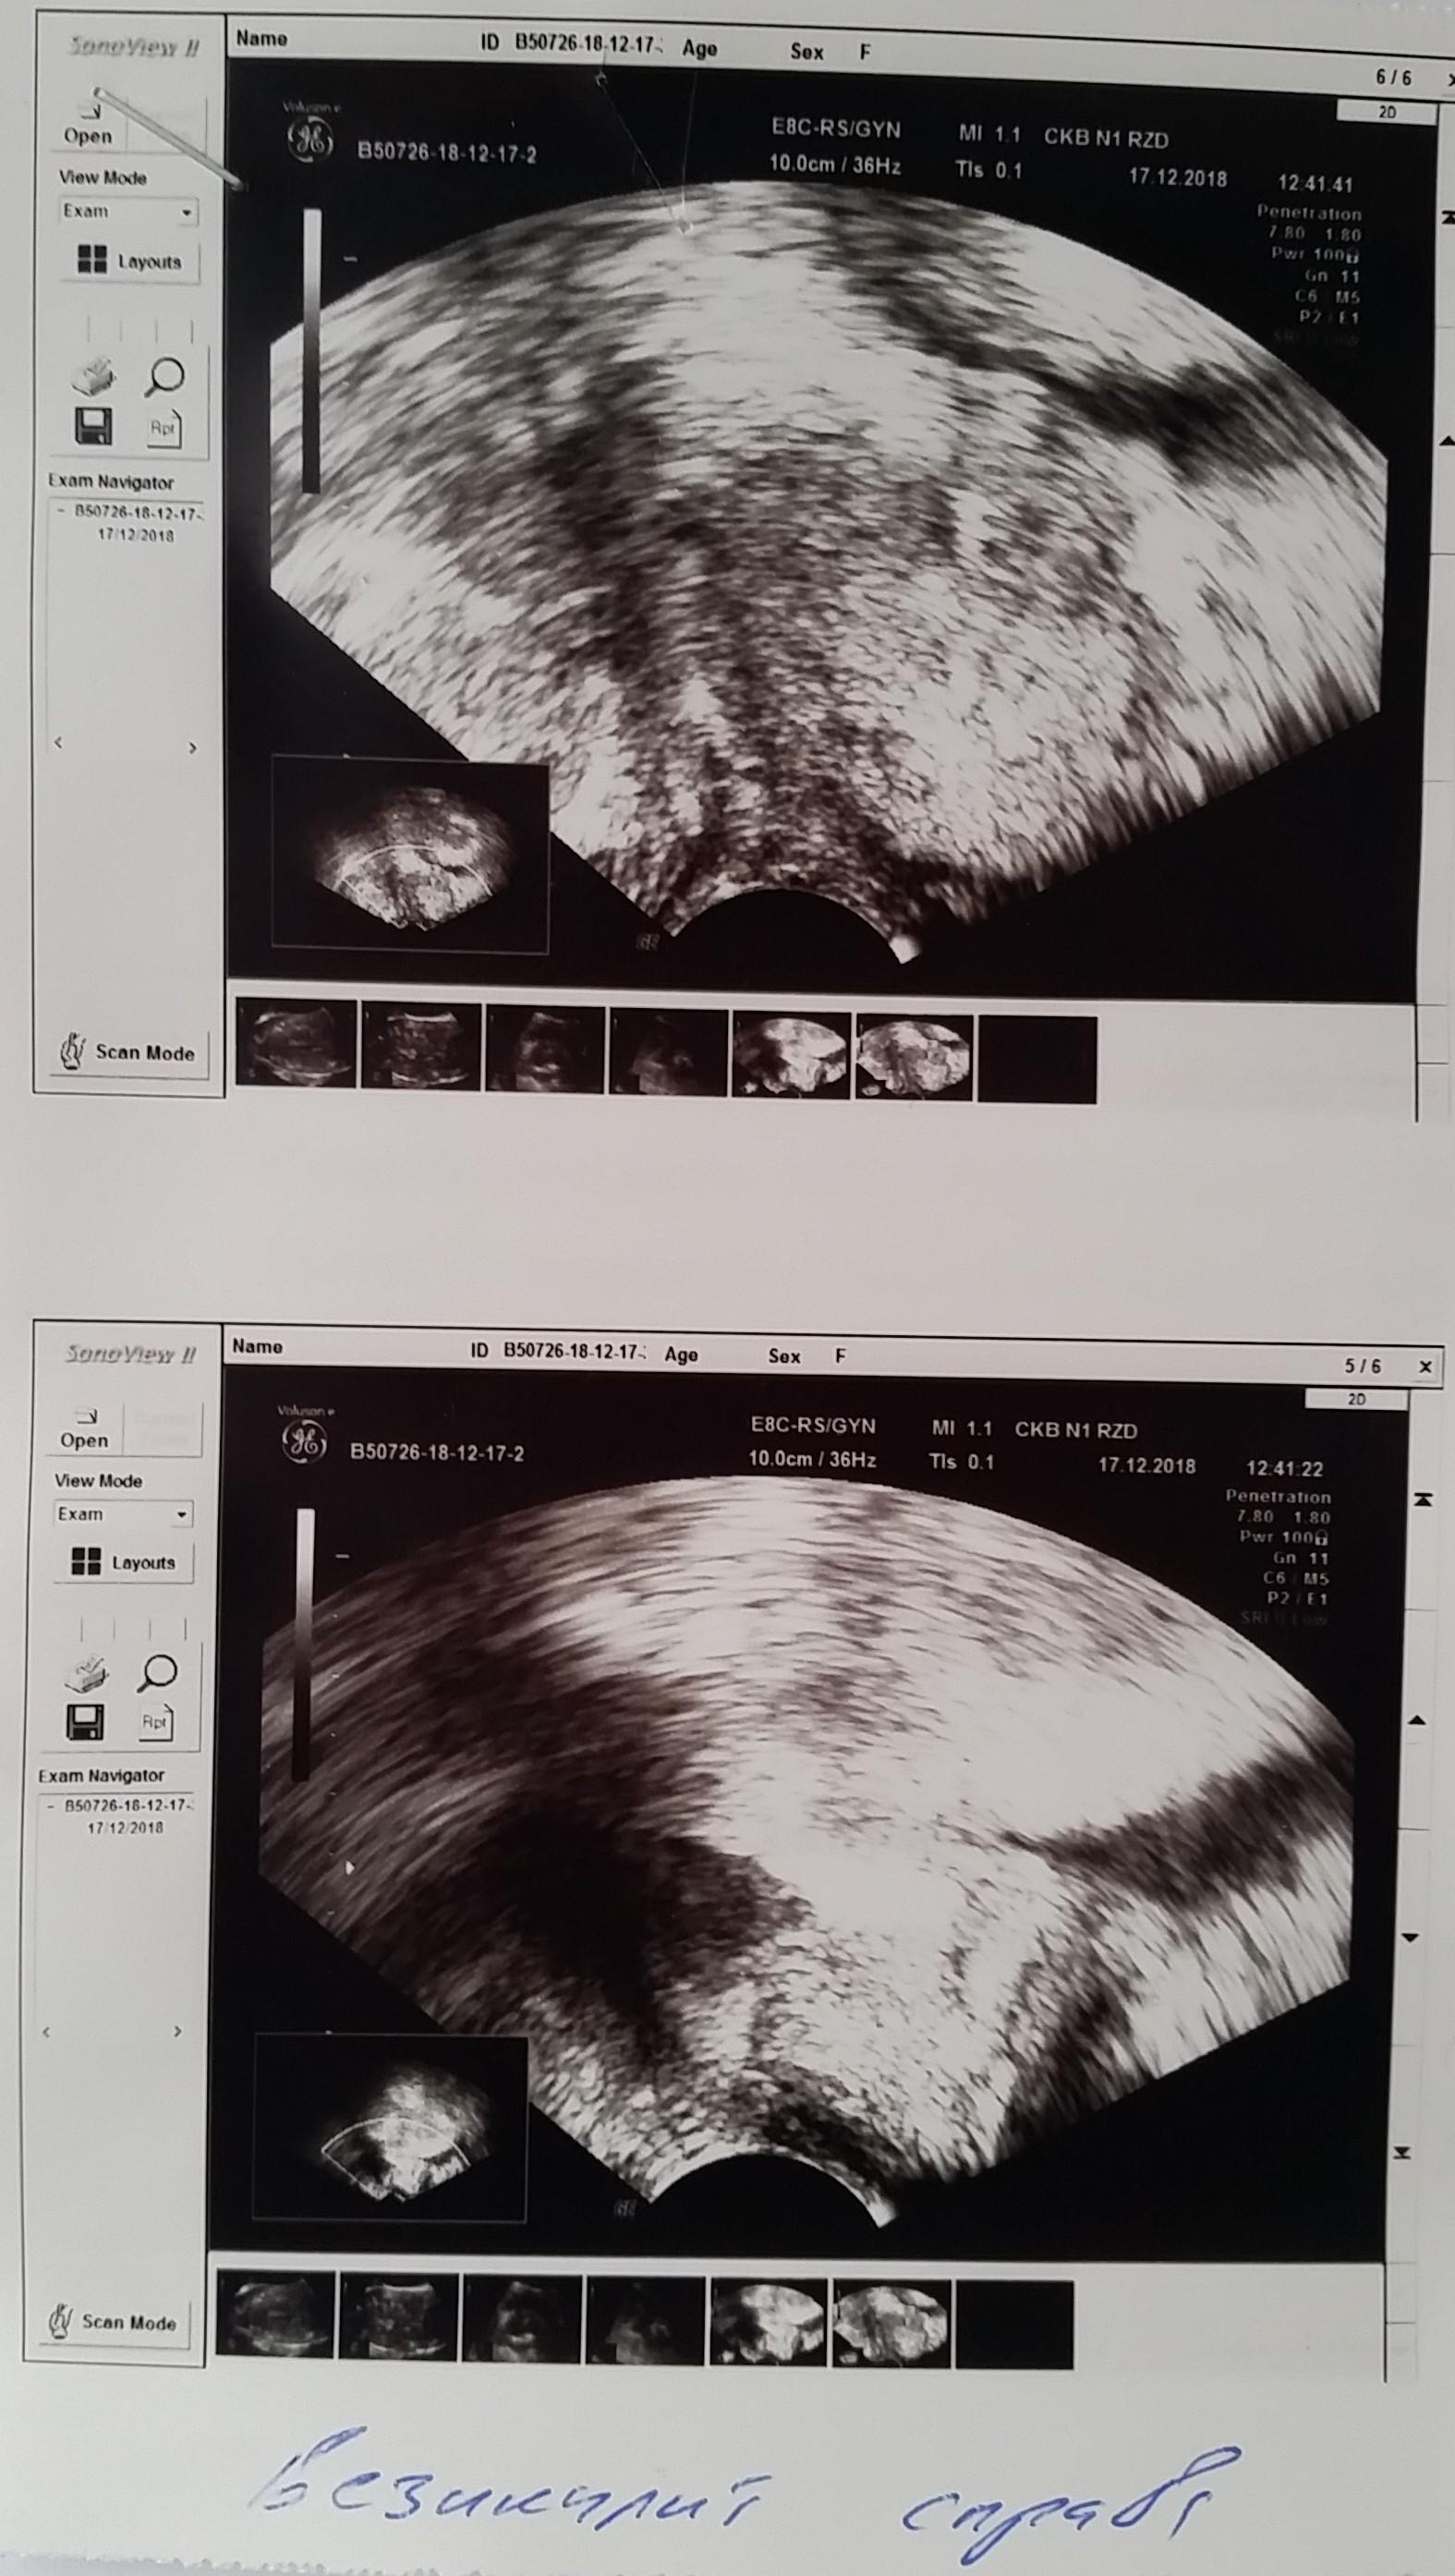

Здравствуйте. Мне 29 лет. Вес 60 кг. Рост 174см. Пол мужской. Беспокоят частые позывы к мочеиспусканию уже где-то пол года. От 6-8 раз в сутки. Раньше столько не ходил. Чувствую что мочевой пузырь не совсем полный. Где то 100-150мл и бегаю в туалет. Очень давно при прыжках с небольшой высоты была резкая боль в промежности. Сейчас очень редко бывает, не знаю простата это болит или что-то другое. Ночью встаю 1 раз. Струя нормальная. Делал УЗИ несколько раз. Врач пальцем проверил простату, сказал, что с левой стороны прощупываются неровности. Боли при ощупывании не было, было чувство на головке, как будто позыв к мочеиспусканию сильный. Сразу ершиком взял анализ ПЦР на инфекции. Нашли только гарднерелла. Сразу начал выписывать антибиотик. Я сказал, не лучше будет на чувствительность сделать анализ. Сказал, зачем терять время. У меня во вложении назначение, ответы анализа, УЗИ.

5. Из клиники только частые позывы. Есть какие то изменения в простате по УЗИ, но я до сих пор сомневаюсь есть ли у меня хр. простатит и какой именно(синдром тазовой боли, инфекционный и др.). Что еще нужно сделать, чтобы определиться с причиной частых позывов?